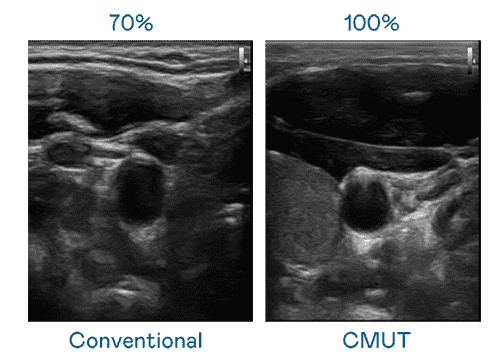

CMUT 技术是一种用电容式微机电元件来产生超音波讯号的技术。。。与传统 PZT 压电式技术相比,,,,CMUT 频宽增加 30%,,更宽频的超音波讯号让影像解析度大幅提升,,是实现高影像品质医疗超音波扫描、、促进精准医疗发展的关键技术。。

大频宽带来超清晰影像

超音波影像的解析度高低,,,,首先取决于探头能发出的讯号频宽。。。。尊龙集团 CMUT 可提供高清晰的超音波讯号,,提供高频宽、、、高灵敏度、、影像纹理细节更高的超音波影像,,,协助医护人员缩短影像判读时间及利用精准的医疗影像进行诊断。。。。